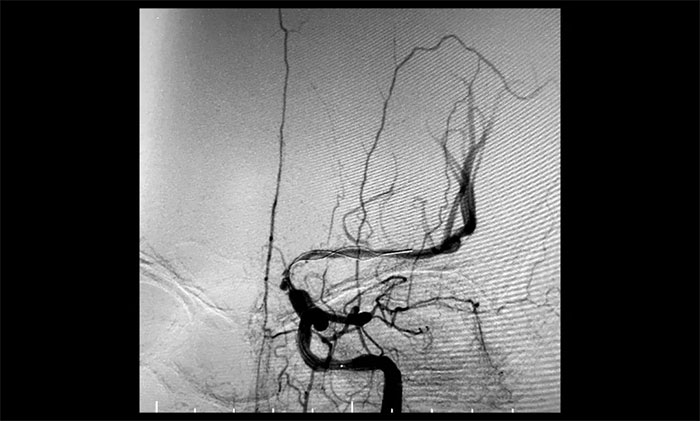

经微导丝成功进入狭窄、闭塞颈内动脉,在支架保护下,进行球囊逐段扩张,支架置入……,经多次球囊扩张,置入支架后,造影显示左颈内动脉起始段狭窄明显改善,左颈内动脉颅内段顺利再通,左颈内动脉眼动脉段、后交通段狭窄明显改善。造影及3D造影见左颈总动脉、左颈内动脉、左大脑中动脉显影可,行支架CT见颅内支架成形可,手术取得成功!

▲ 术后,右颈内动脉起始段狭窄明显改善